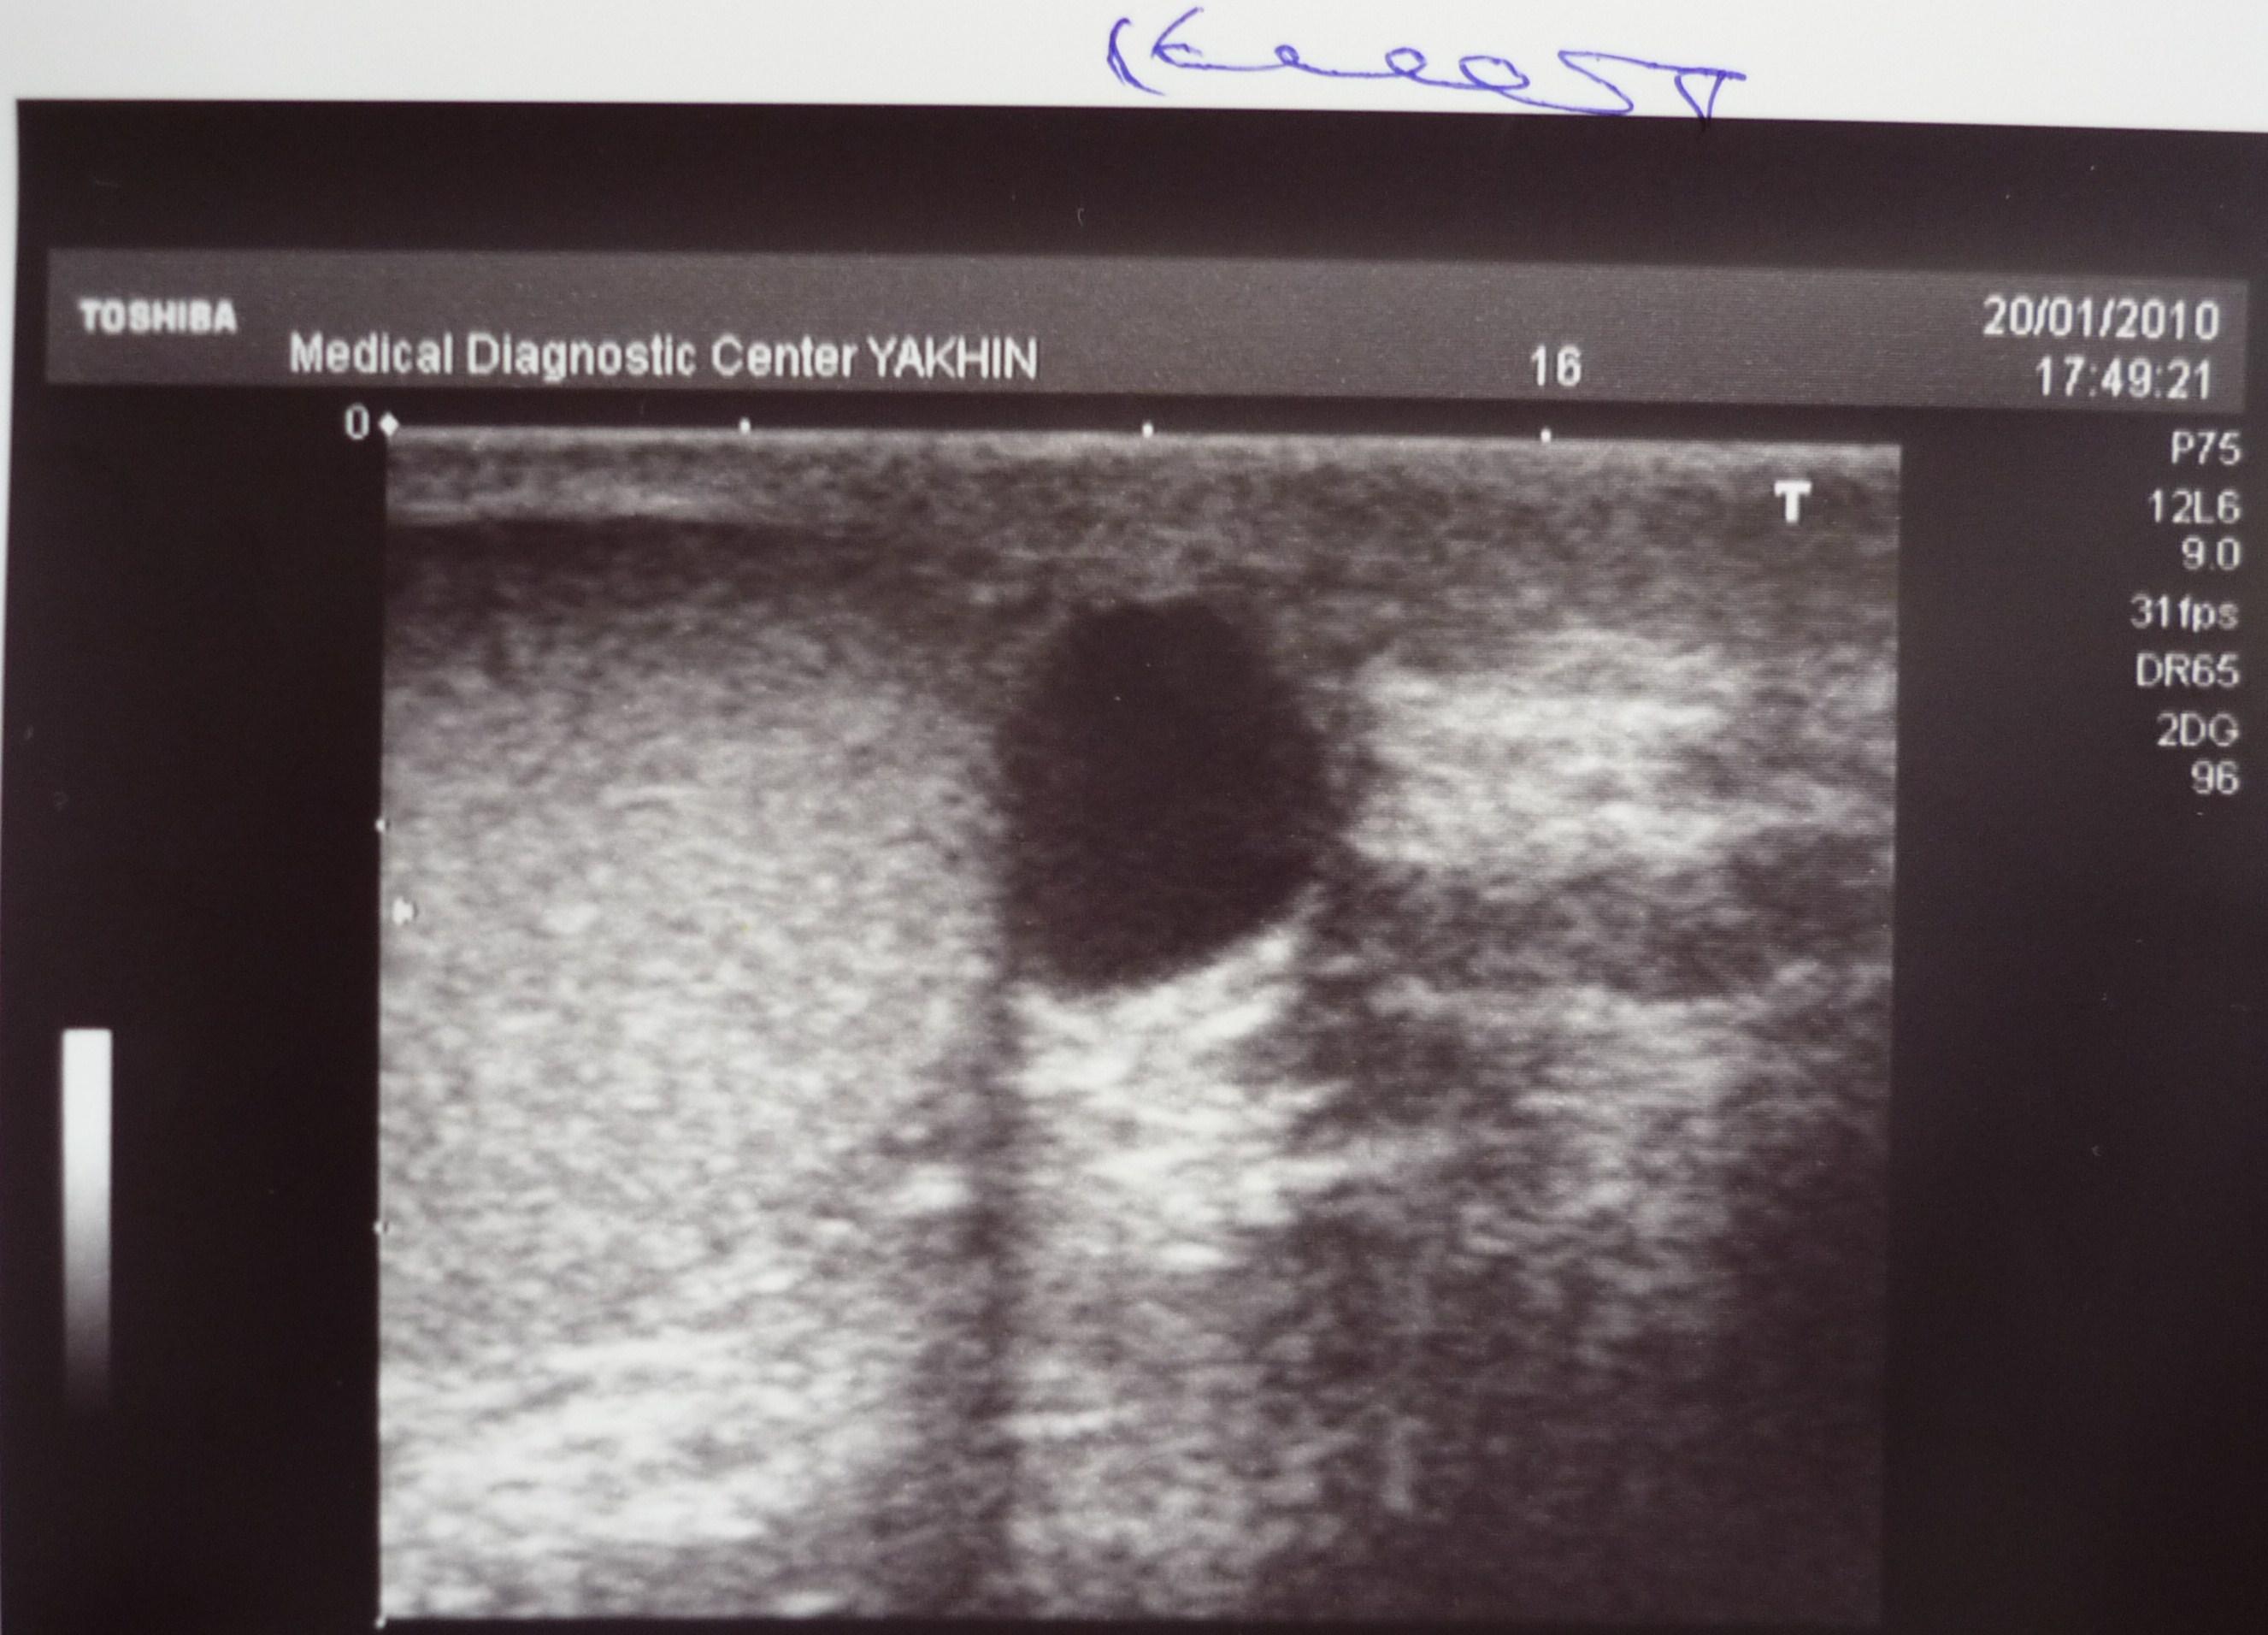

Здравствуйте! На днях сделал УЗИ органов мошонки с доплерографией. "Впечатлило". Три патологии сразу! Выраженное варикоцеле слева. Киста правого яичка. Водянка слева. Какими могут быть мои дальнейшие действия? Что посоветуете? Три операции сразу или же есть другие варианты? Обрекает ли это меня на бесплодие,есть ли возможность стать отцом?